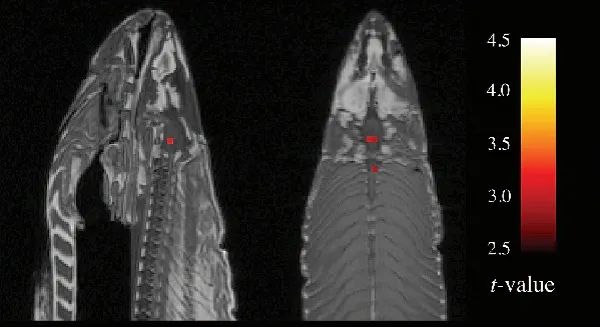

这个令人难忘的针对功能磁共振成像技术(fMRI)的驳斥出现在一次神经科学会议上。

fMRI能够帮助神经科学家探索哪些大脑区域参与了哪些认知,典型的研究会比较对象和对照组的fMRI图像,并思考为什么大脑的某些部分亮度有所不同。

但是,实验软件必须对评估结果的统计学意义做出假设。而最近的一项研究表明,这些假设有时会严重夸大差异。问题已经暴露,但科学家们并未对这个问题的严重性达成一致。

于是一份标题为《通过死大西洋鲑鱼研究人类神经活动:论多重比较校正的重要性》的学术墙报登场了。你没看错:一条死鲑鱼

这是一个故意为之的愚蠢实验。研究人员跟那条死鱼交谈,还给它看了人们在不同社交环境中的照片。结果令人震惊。当鲑鱼被问及人们的情绪时,影像显示它脑干的几个区域表现出来的活跃性高于它在“休息”时的活跃性。

图片

这还只是对人类社交场景的“反应”,想象一下,如果这条鲑鱼被问及鲑鱼的情绪,这些区域会多么明亮。

要么是我们在死鱼认知方面取得了惊人发现,要么是我们未经修正的统计方法出了问题。